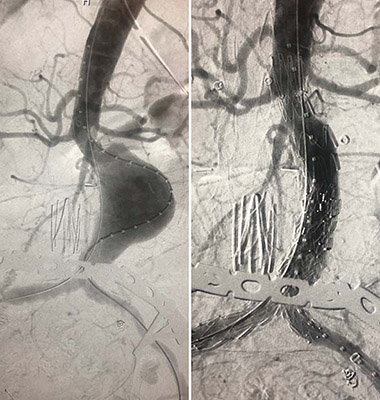

(A) An abdominal aortic aneurysm (AAA) before repair. (B) The same AAA after deployment of the TREO endograft.

Recently, a team at the University of Maryland (UM) Center for Aortic Disease was among the first three in the nation - all on the same day - and the first in the mid-Atlantic region to complete an endovascular aortic abdominal aneurysm (AAA) repair with the TREO® endograft three-piece modular system (Terumo Aortic (US), formerly Bolton Medical, Sunrise, FL), which gained FDA approval this past May. The endovascular aortic aneurysm repair (EVAR) procedure was led by vascular surgeon Khanjan H. Nagarsheth, MD, Assistant Professor of Surgery at the University of Maryland School of Medicine.

Unlike other off-the-shelf endovascular devices, the three-piece TREO permits numerous configurations that can be customized to the patient’s anatomy more precisely. The TREO’s main stent-graft consists of a proximal section – the length of which can be adjusted when deployed into the aneurysmal sac – with a bifurcation to accommodate the iliac arteries. This main stent-graft is available in eight diameters ranging from 20 to 36 mm to better match the patient’s aortic anatomy. Through the bifurcated portion of the graft, two separate leg extensions are fitted and deployed into the iliac arteries. These extensions offer the surgeon distal diameter options of 9 mm, 11 mm and 13 mm so the appropriate size can be selected at each portion of the stented artery.